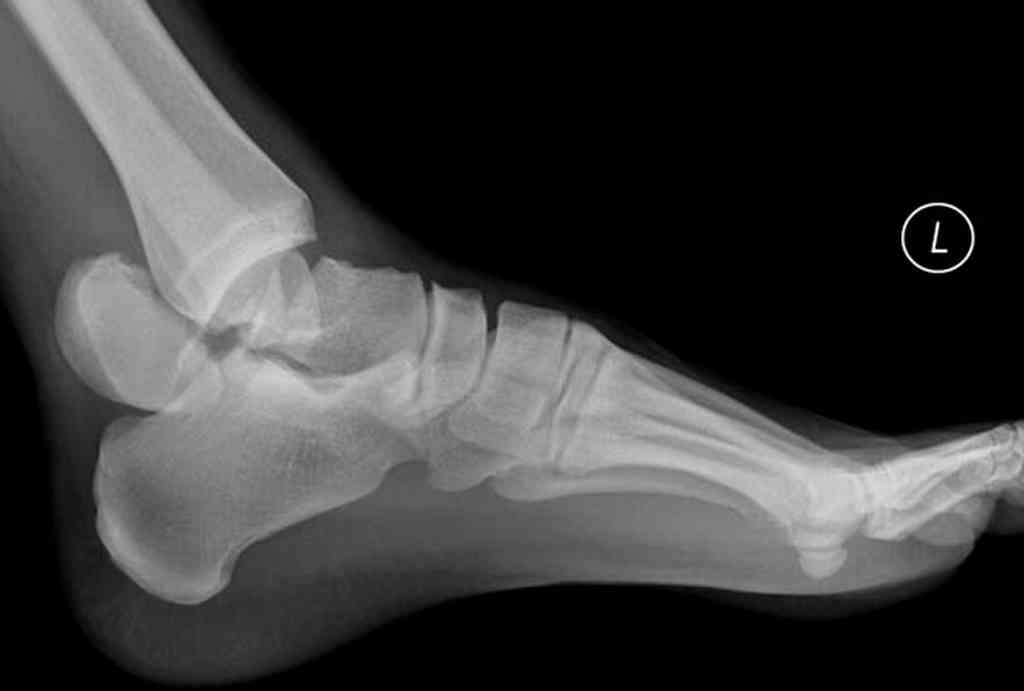

При лечении переломов шейки таранной кости очень важно увидеть вторую проекцию шейки, только боковой проекции недостаточно.

В приложении укладка Канале.

С ув Коробкшкин Г